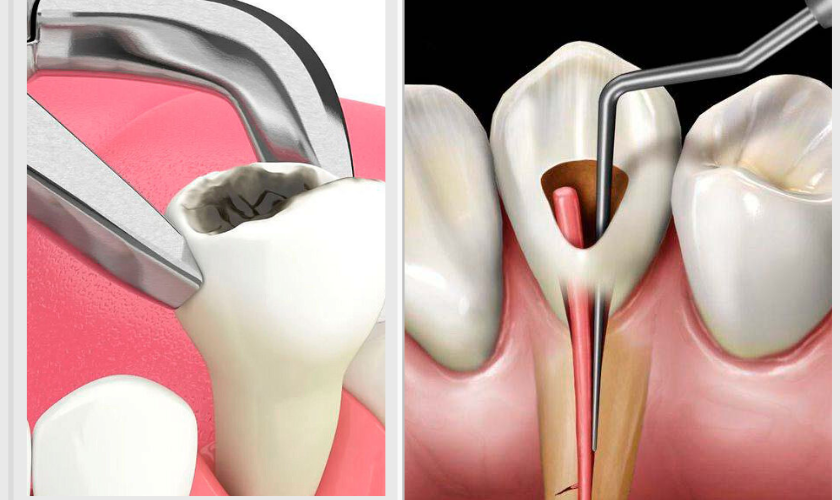

In contrast, tooth extraction removes the entire tooth structure. While extraction resolves infection or pain, it introduces considerations such as bone resorption, adjacent tooth movement, and the need for prosthetic replacements like implants or bridges.

Despite the advantages of preservation, there are scenarios where Root Canal Treatment or Tooth Extraction may lean toward extraction. Severely fractured teeth, extensive decay compromising structural integrity, or failed previous endodontic treatments may make tooth removal the most viable solution.

Extraction may also be preferred when periodontal disease has caused significant bone loss, or when patient-specific factors such as systemic health, immune response, or inability to maintain oral hygiene increase the risk of failure. Understanding these clinical indicators helps patients make informed decisions rather than relying solely on anecdotal advice.

Tooth extraction, while sometimes unavoidable, carries potential complications. Immediate issues can include excessive bleeding, pain, and swelling. Long-term effects may involve bone resorption, shifting of adjacent teeth, and compromised chewing function.

In some cases, extraction sites may require grafting or implant placement to restore aesthetics and function. Comparing these potential complications with the relatively predictable outcomes of Root Canal Treatment or Tooth Extraction highlights the benefits of attempting tooth preservation first.

Although preservation is ideal, Root Canal Treatment or Tooth Extraction decisions sometimes favor extraction. Indications include severe tooth decay, non-restorable fractures, failed prior root canal treatment with persistent infection, or compromised bone support.

Even in these cases, planning for replacement with implants or bridges can restore function and aesthetics. Extraction decisions should be guided by clinical evaluation, patient preferences, and long-term prognosis, balancing immediate relief with long-term oral health.